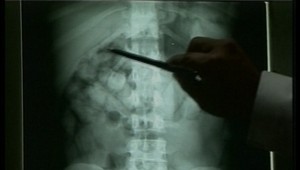

Tridsaťročného Nigérijčana policajti zadržali v utorok podvečer, keď priletel zo Španielska. Cudzinca ihneď po prílete kontrolovali colníci. V brušnej dutine mal 78 balíčkov, predbežná expertíza potvrdila, že ide o viac ako 1 400 gramov kokaínu.